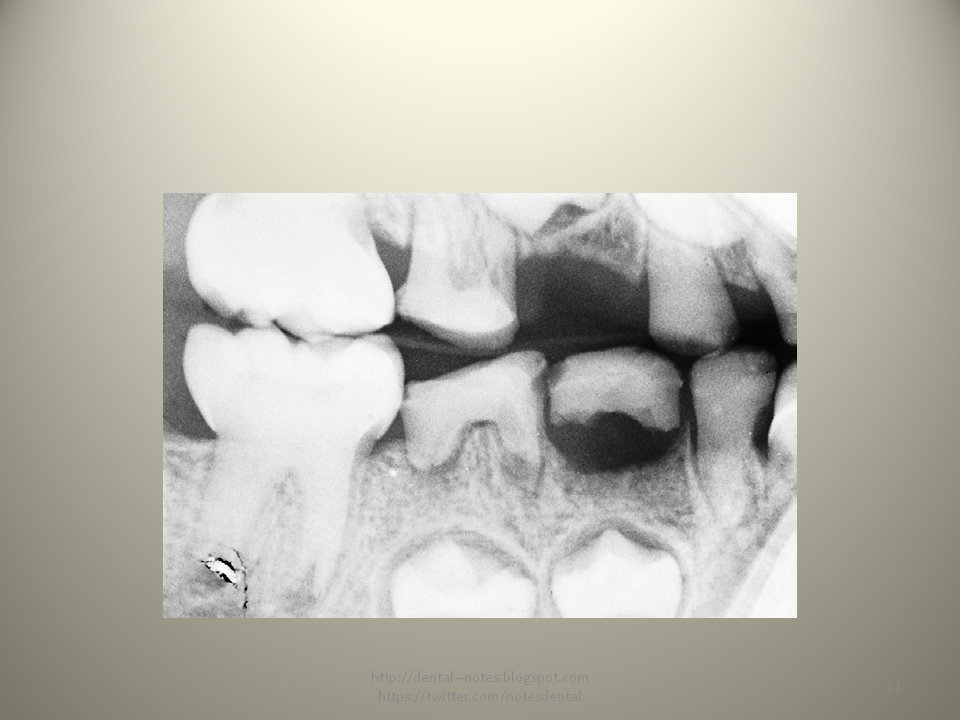

Наследственные проблемы с зубами: причины и профилактика